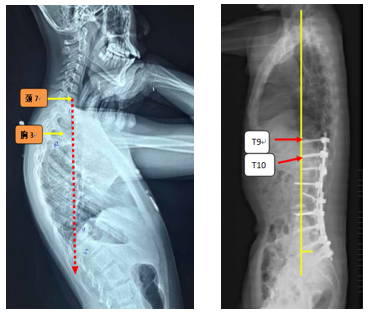

(2)上固定椎在交界区或存在交界性后凸

图6 长节段融合固定上固定椎(UIV)选择在胸10-12胸腰椎交界区是PJK的风险因素之一

图7 术前-术后1个月-术后1个月外观